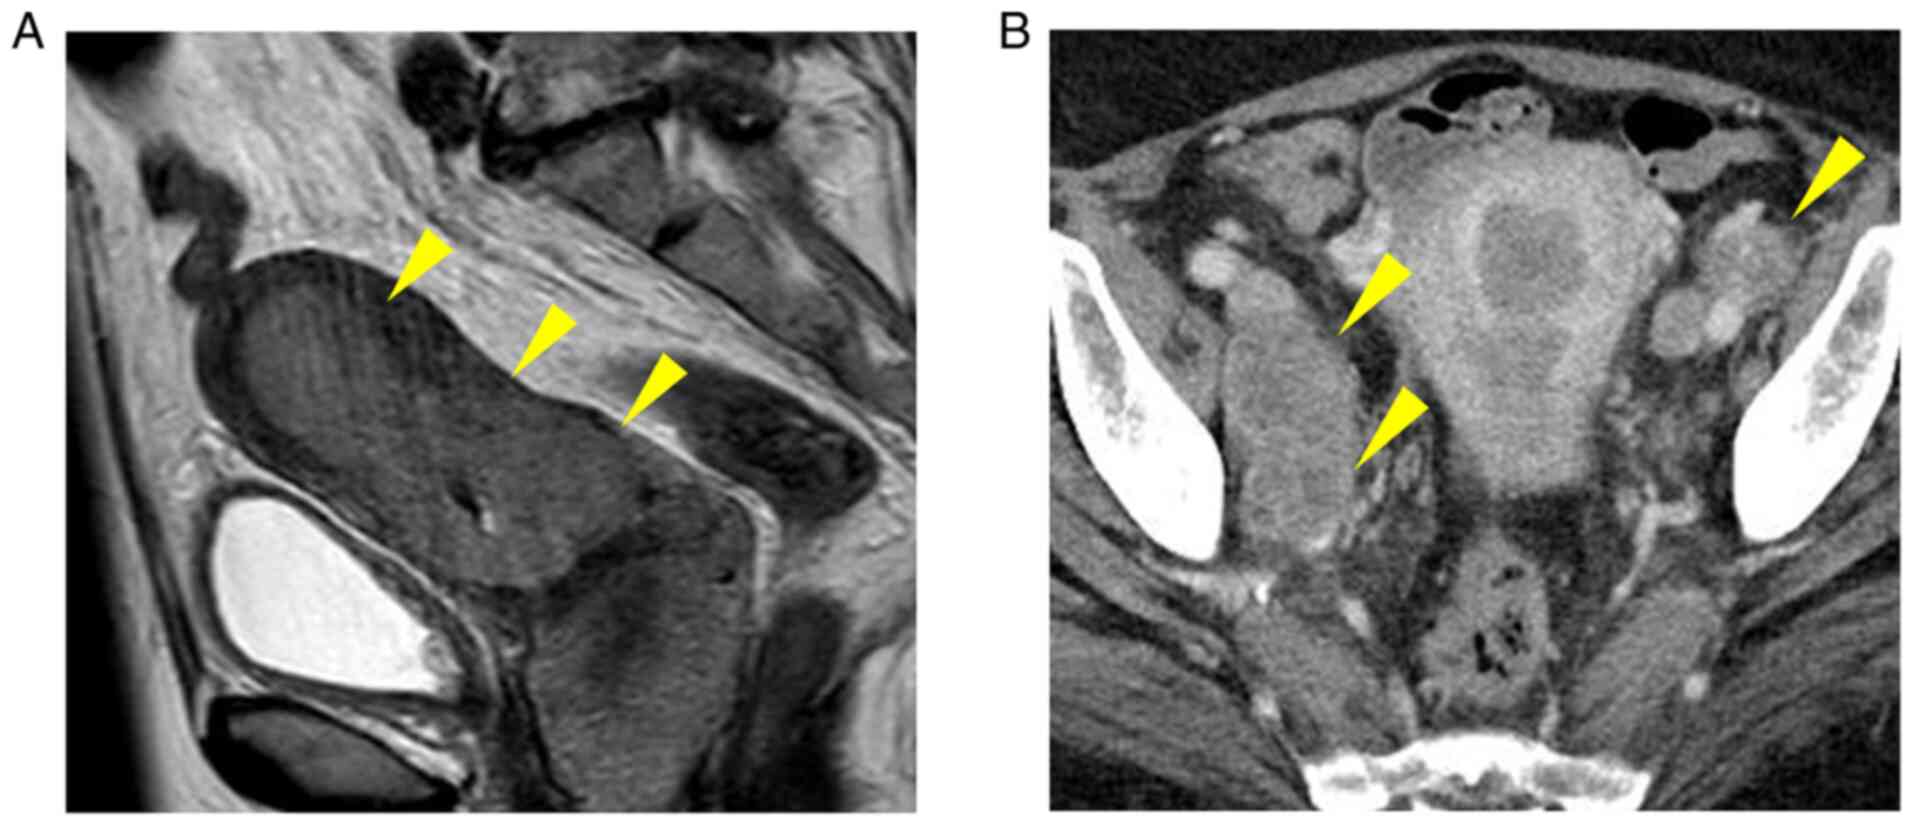

Durable response after the discontinuation of pembrolizumab treatment due to an adverse event in a patient with advanced endometrial cancer: A case report

The persistence of antitumor effects has been reported after the completion of treatment with immune checkpoint inhibitors (ICIs) for various types of carcinoma, such as malignant melanoma, exhibiting a durable response. A durable response has also been noted after the discontinuation of treatment at an early stage due to adverse events, including in renal pelvic cancer, pancreatic cancer and intrahepatic cholangiocarcinoma; however, to the best of our knowledge, a similar case report has not yet been published in the malignant gynecological tumor field. The present study described a patient with refractory advanced endometrial cancer in whom the administration of pembrolizumab was discontinued after the completion of the 7th course due to renal dysfunction; however, persistent tumor‑reducing effects and decreases in the levels of tumor markers were noted for more than 18 months after the cessation of treatment. Pembrolizumab may be continuously administered to some patients for a long period, whereas a durable response is achieved by others even after its discontinuation at an early stage; therefore, difficulties are associated with selecting an appropriate duration of administration. Further studies are required to search for biomarkers that facilitate high‑accuracy effect predictions, and to establish an optimal administration period in consideration of specific adverse reactions to ICIs and cost‑effectiveness.

Figure 1